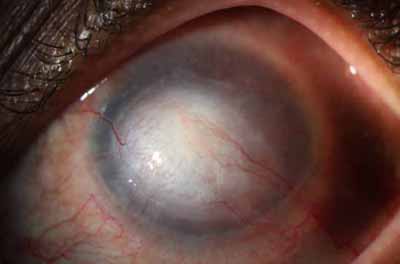

En su evolución se observará aumento del edema, aparición de un anillo inmunológico (Wessely), agrandamiento y coalescencia de los infiltrados que progresan hacia la formación de un absceso, queratolisis superficial, adelgazamiento y perforación corneal.

Anillo inmunológico de Wessely

- Es la expresión de la interacción de los antígenos extraños con los anticuerpos que se difunden desde los vasos limbares hacia el estroma.

- Representa la formación de un complejo inmune que activa el sistema del complemento.

- El anillo de Wessely contiene principalmente neutrófilos

La vascularización y el hipopion son poco frecuentes en los estadios tempranos de la queratitis. Con el tiempo, en los estados avanzados de invasión estromal, aparecen vasos estromales